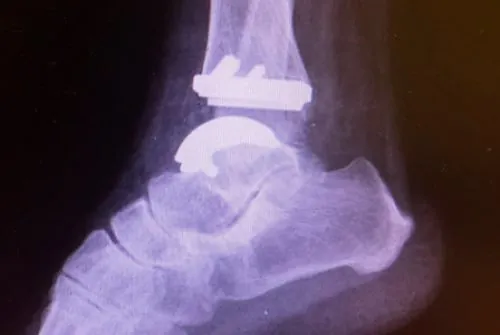

Hoje em dia, em grande parte dos casos, realizamos a artroplastia do tornozelo, quando se faz a substituição da articulação doente (tornozelo com artrose) por uma articulação metálica (prótese de tornozelo). Neste tipo de tratamento obtemos a melhora da dor com a manutenção do movimento articular.